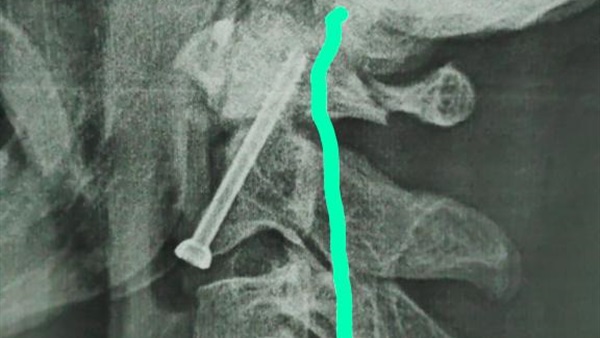

واوضح الدكتور حمدي سعد مدير المستشفي الجامعي انه بعد اجراء الفحوصات والاشاعات اللازمة للمريض تبين وجود كسر في الفقرة الثانية من العمود الفقري الرقبي، ويحتاج إلى جراحة عاجلة لتثبيت الفقرة العنقية، حيث كان هذا الكسر يشكل خطراً كبيراً على النخاع الشوكي وحياه المريض.

وذكر الدكتور عبدالرحمن الشيخ رئيس قسم جراحة العظام انه بعد دراسة الحالة في ضوء نتائج الفحوصات الطبية، تم اتخاذ كافة التدابير التحضيرية للعملية، لافتاً الي ان الفريق الطبي الذي إجري العملية الجراحية للمريض كان تحت اشراف الدكتور أحمد صالح أستاذ جراحة العظام والعمود الفقري، حيث تم تثبيت الكسر بنجاح، و بدأ المريض الحركة بحرية تامة بمفرده بدون اي وسائل مساعدة.